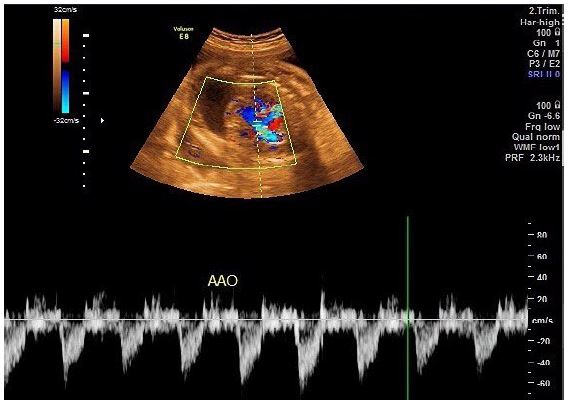

A transabdominal fetal echocardiogram performed at 27 weeks of gestation revealed an abnormal cardiac axis, ventricular asymmetry with a smaller right ventricle, and severe calcifications of the tricuspid valve, pulmonary valve, and descending aorta (Figure 1). Cardiac function was borderline, with considerable pericardial effusion and a circumferential myocardial performance index within normal limits for the left ventricle. The four-chamber view was abnormal, with atrioventricular and semilunar valve dysfunction likely secondary to progressive calcification of the great vessels (Figure 2). The fetal heart rate was 145 beats per minute in sinus rhythm.

Figure 1: Clinical image.